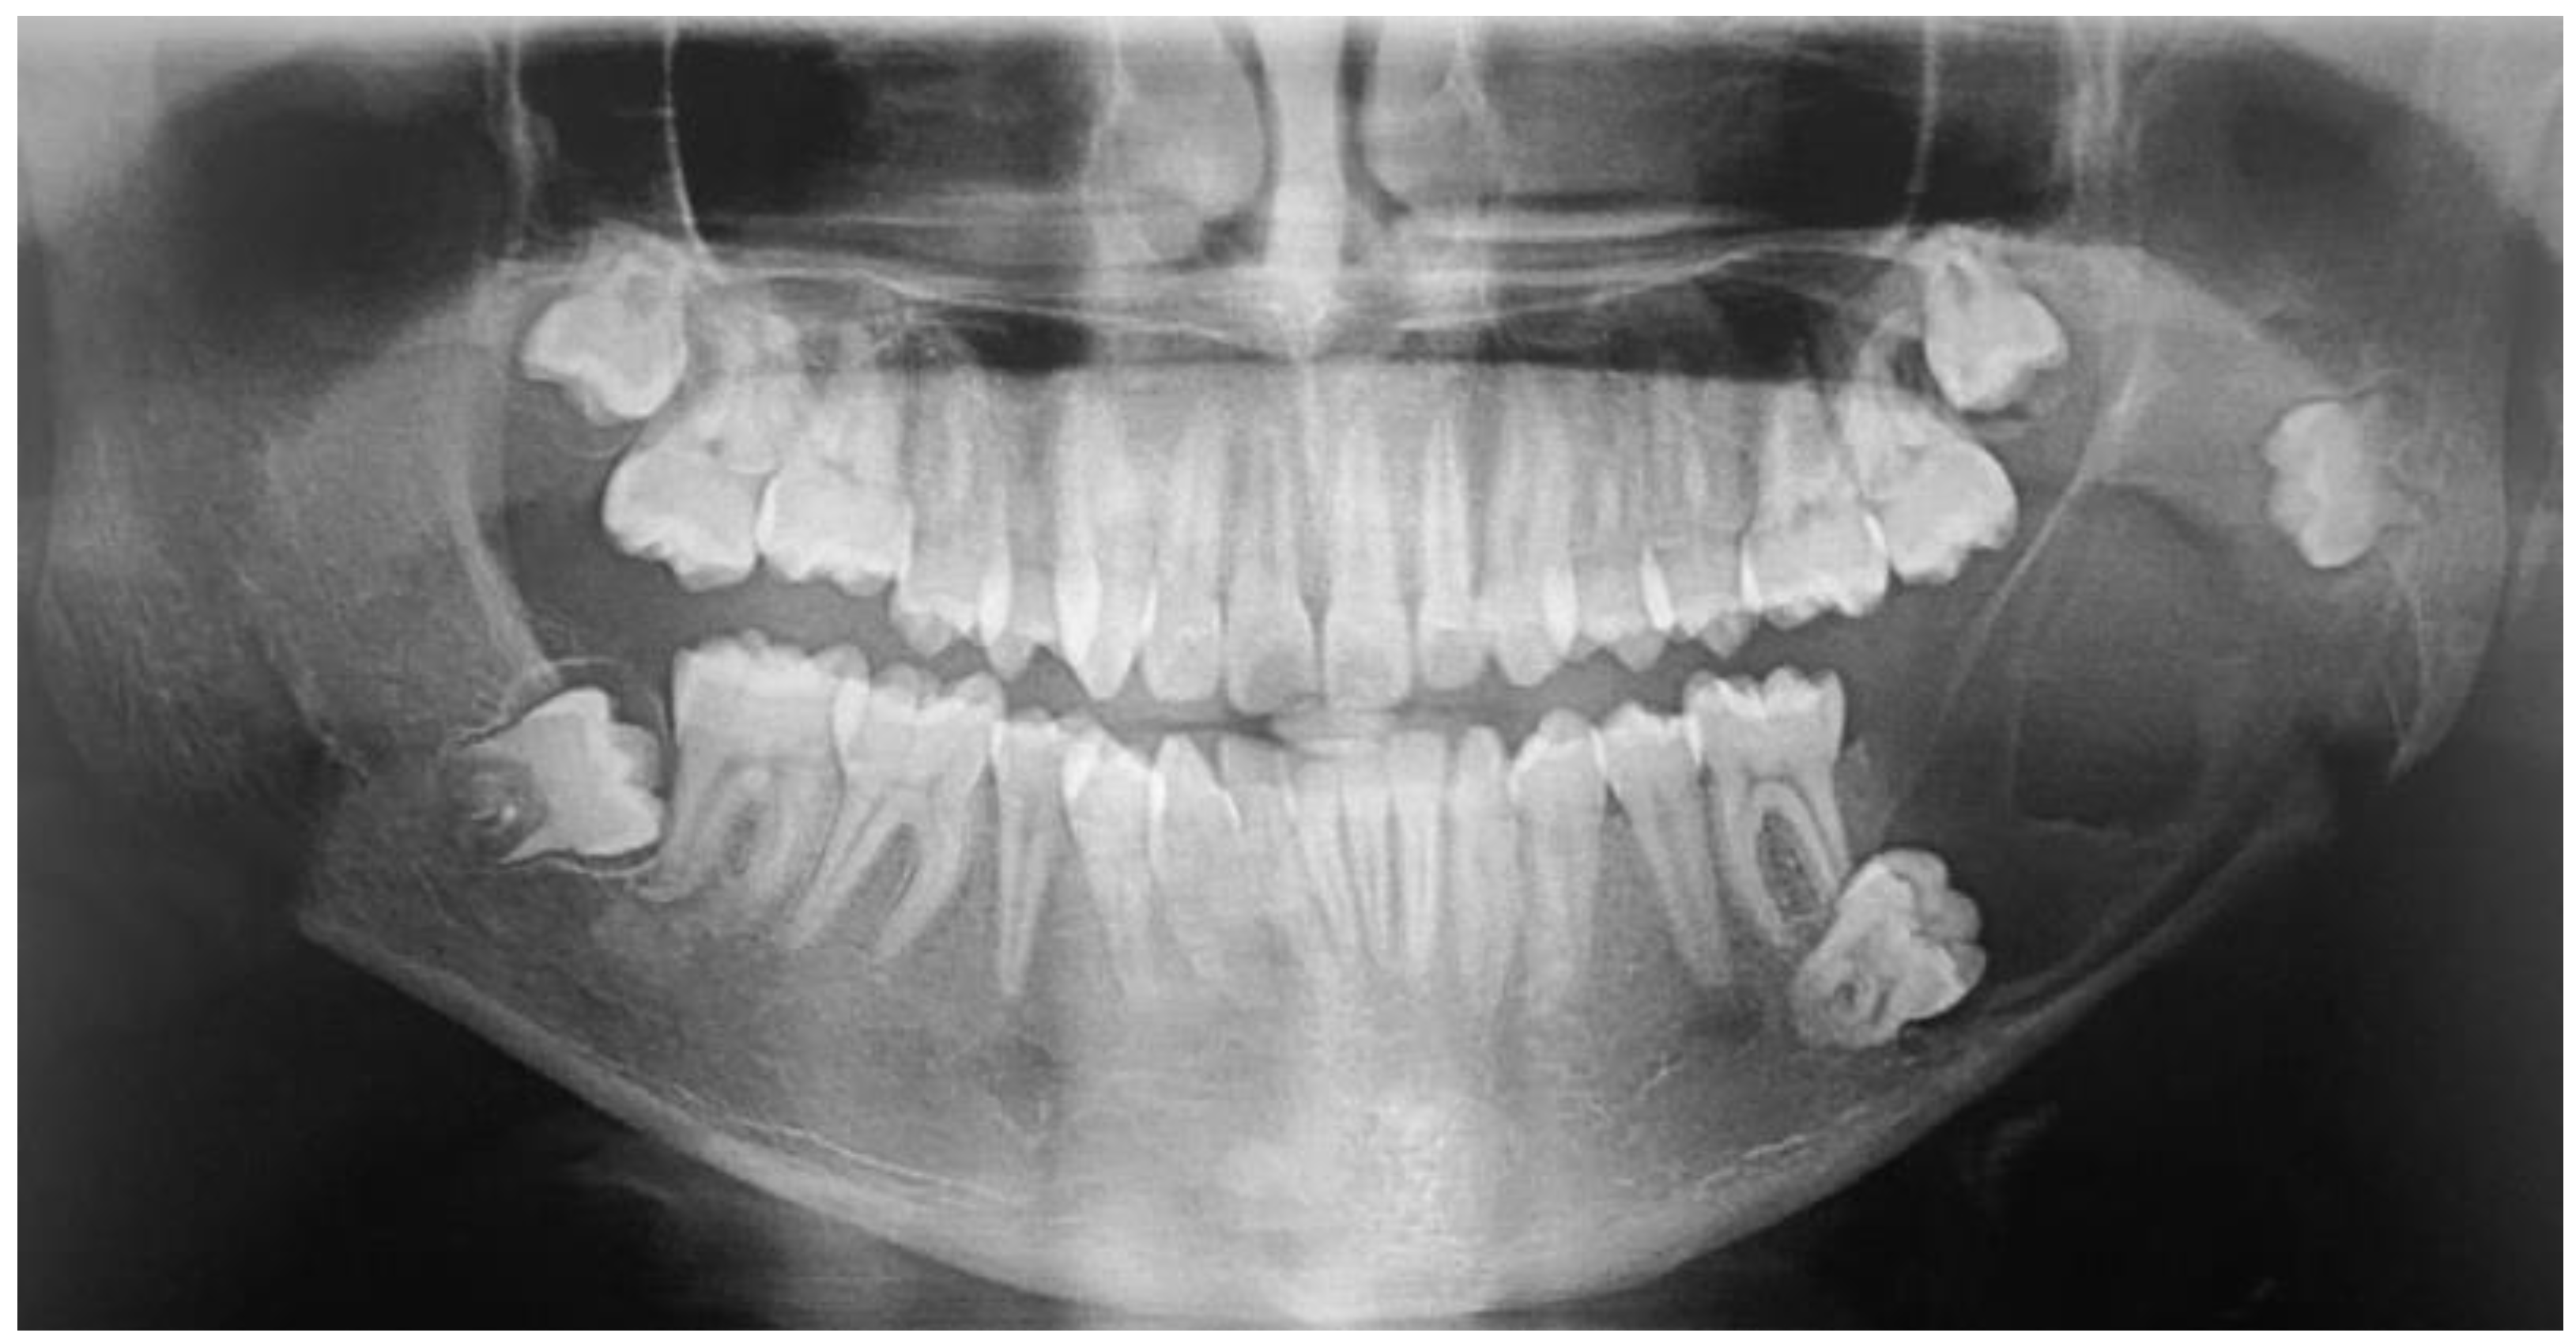

2.1. Case 1